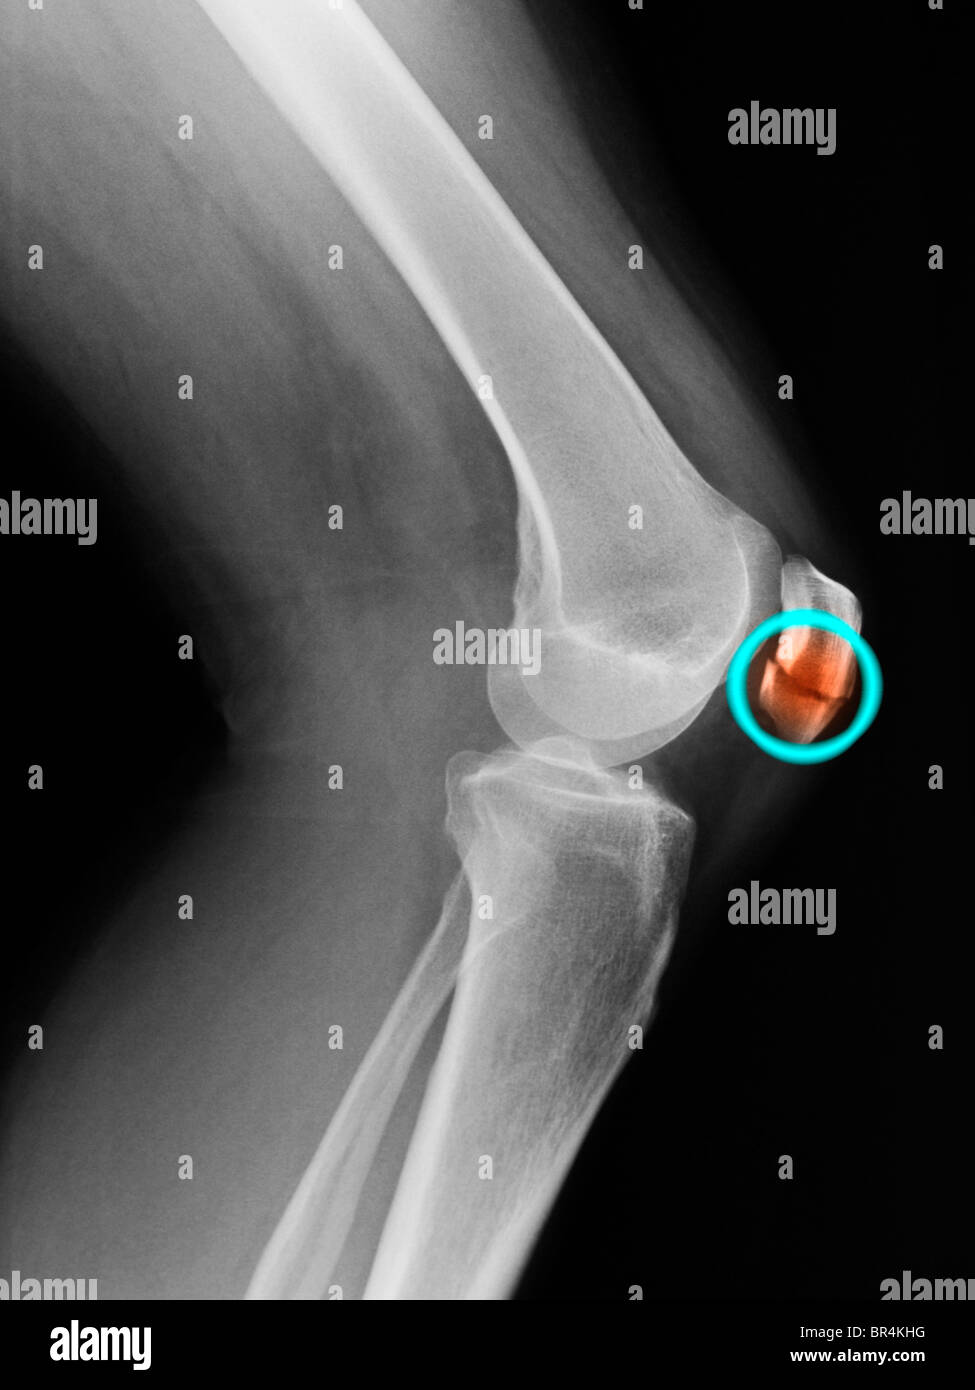

From www.alamyimages.fr

Fracture de la rotule Banque d'images noir et blanc Alamy Fracture De La Rotule Du Genou  Le traitement d'une fracture du genou dépend de sa gravité : Lors de ce type de traumatisme, l’articulation saigne de l’intérieur, ce qui provoque dans tous les cas un gonflement à l’avant de l’articulation. Le trait de fracture est le plus fréquemment transverse, en plein corps de la rotule, traversant ainsi la surface cartilagineuse, il s’agit donc d’une articulaire pouvant. Fracture De La Rotule Du Genou.